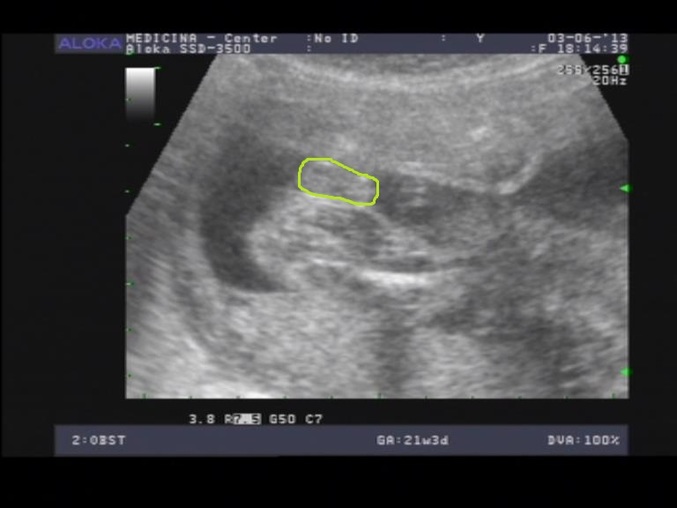

спасибо! просто писи в 1 и 2 Б отличаются,вот и закрались сомнения))) но,видимо,все же опять мужик...

1 Б

2 Б

в первый раз четко писька была видна,а сейчас толщина то наравне с мошонкой))) вот такие у меня загоны)))